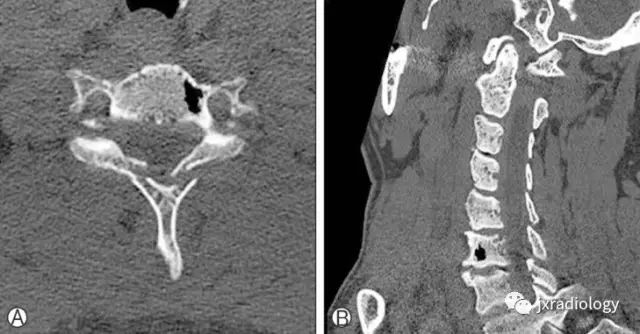

影像资料:

CT:被认为是最好的诊断方法,CT值约-800~-1000HU,椎体及椎间隙内可见气体可以看到相连续的层面,有时会向硬膜外扩张。MRI:气体在T1及T2均为低信号,易和硬化性病变混淆,CT有助于诊断。随访发现一些病灶会增大,但不需要特别治疗。